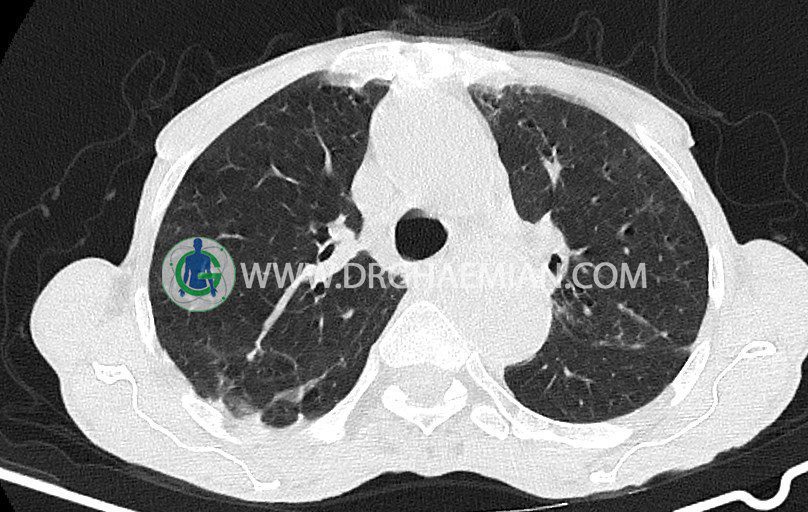

سی تی اسکن ریه یک روش تصویربرداری است که با استفاده از اشعه ایکس تصاویر عرضی مقطعی از ریه و بالا تنه ایجاد می کند. در این کیس برونشيوليت، برونشکتازی سیستیک و سیلندریک، دیلاتاسیون آئورت صعودی و کلسیفیکاسیون دیواره آئورت مشاهده می شود.

در سی تی اسکن اسپيرال ريه ها و مدياستن بدون کنتراست وريدی (مولتي ديدکتور 16 با مقاطع ظريف و بازسازي کرونال):

تراشه و برونش های اصلی نرمال اند.

پلورال افيوژن، جابجايی محتويات مدياستن، فيبروز ريوی و Collection مشهود نيست.

– برونشکتازي سيستيک و سيلندريک در سگمان خلفي لوب فوقاني چپ

– ندول هاي ساليد ground glass با توزيع پري برونکيال همراه با برونشکتازي سيلندريک در لينگولا و

در لوب مياني راست و ندول هاي ساليد همراه با tree in bud پراکنده در ريه ها مطرح کننده برونشيوليت

و ضايعات التهابي مثل TB

– ديلاتاسيون آئورت صعودي به قطر 43 mm و

– کلسيفيکاسيون ديواره آئورت و عروق کرونر

مشهود است.